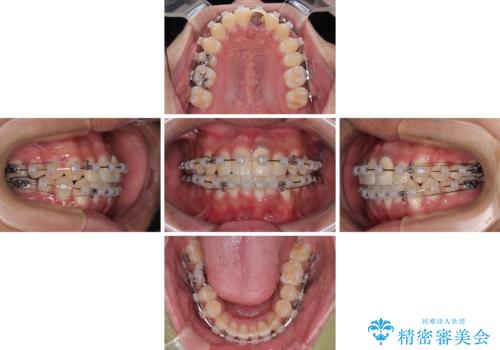

- クリアブラケット

- 1年10ヶ月

上下ともに歯列幅が狭く、その影響でデコボコになっていたため、ワイヤー装置を用いて歯列を側方に拡大しながら、デコボコを解消していくこととしました。